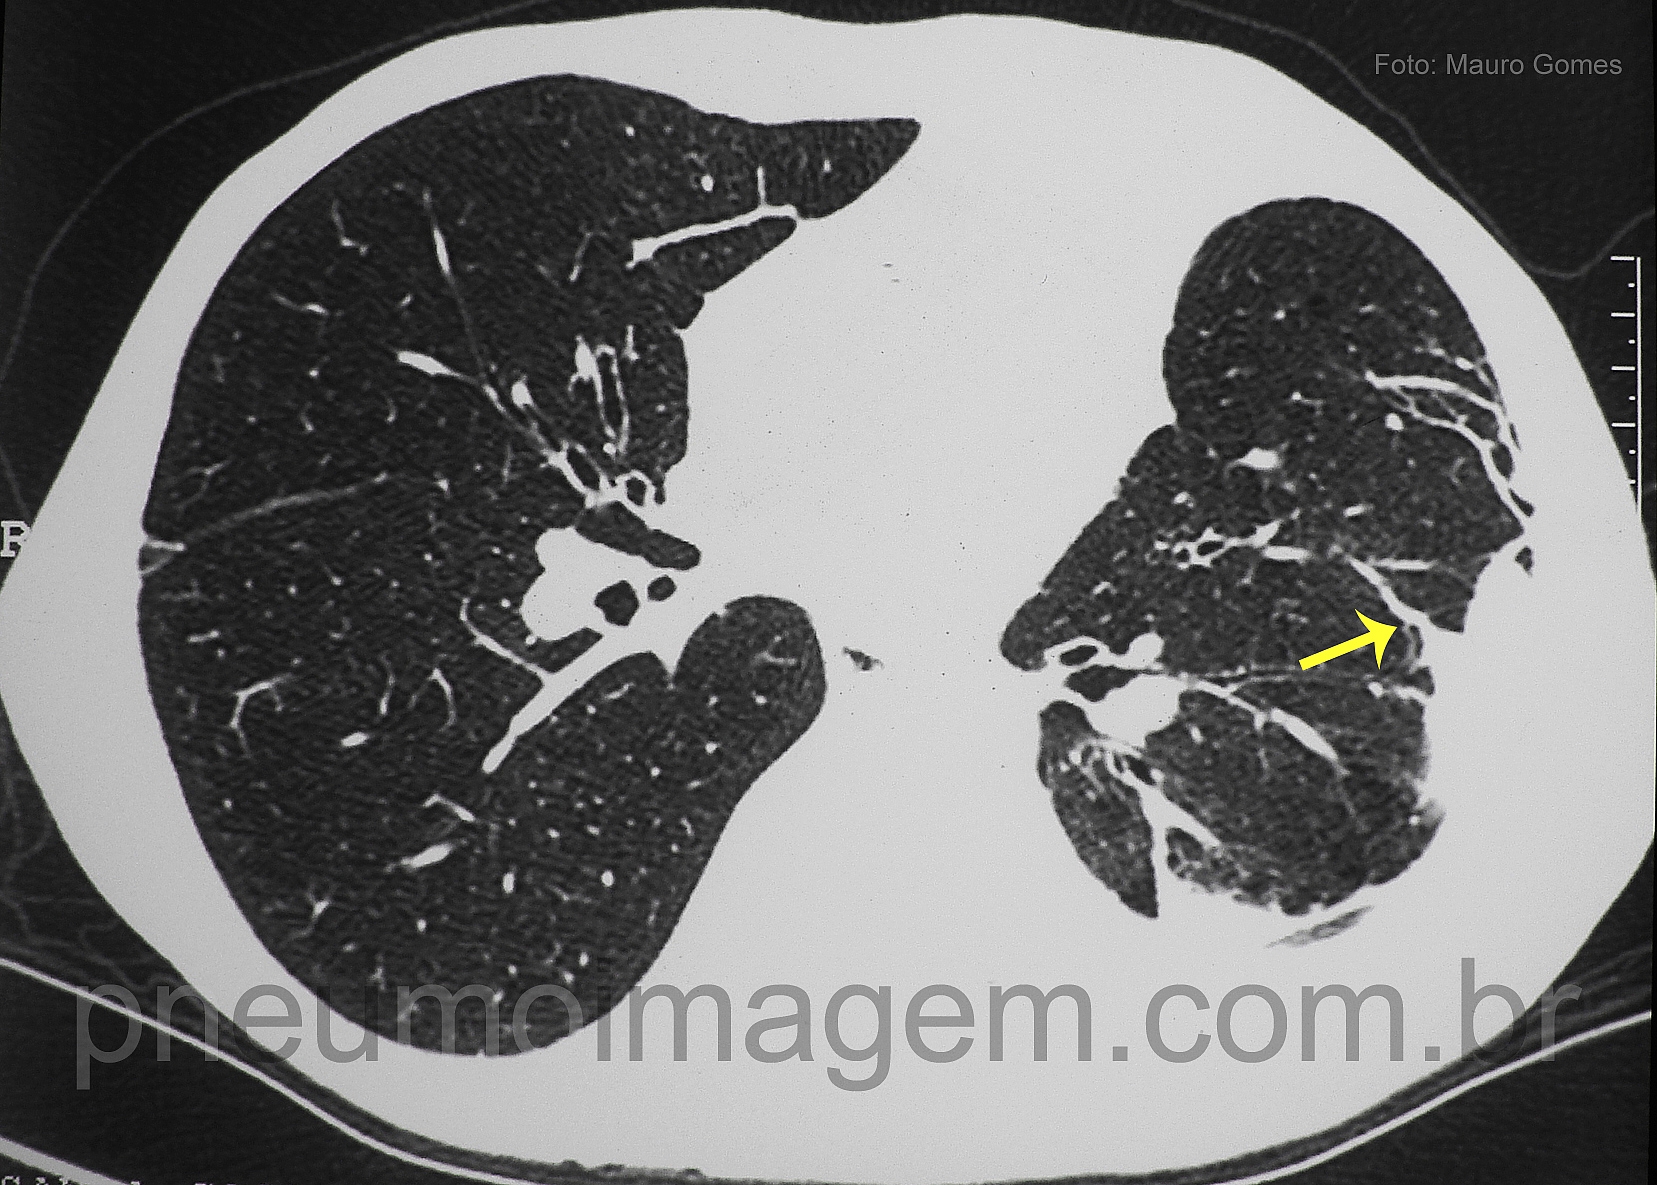

CASO CLÍNICO #28

Aproveitando o clima natalino, o caso desse mês mostra um sinal tomográfico interessante. Qual o nome desse sinal e o que ele significa? Deixe os seus comentários abaixo.

Enjoying the Christmas season, the case of this month shows an interesting tomographic signal. What is the name of the sign and what it means? Give your comments below.